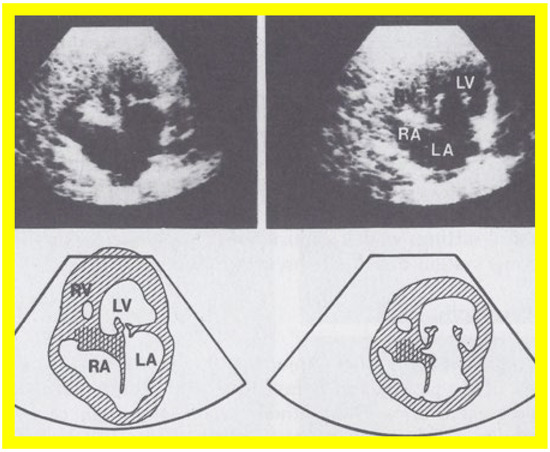

3. Historical Aspects of the Evolution of the Echo of TA

At the time of the preparation of the manuscript for the author’s first edition of the book on tricuspid atresia [23], two dimension (2D) echocardiography was being introduced into clinical practice and the 2D pictures were crude, requiring us to juxtapose line drawings [24] to facilitate interpretation of the figures (Figure 3). The published 2D pictures of TA [25,26], prior to ours, were equally crude. These pictures [24,25,26] represented the state of the art echocardiography machines of that time.

Figure 3. Selected video frames from apical four chamber view of a two dimensional (2D) echocardiographic study, demonstrating a dense band of echoes between the right atrium (RA) and hypoplastic right ventricle (RV). Line drawings are shown beneath the 2D frames. Note that the mitral valve is closed in the left image, while it is open in the right image. The atretic tricuspid valve echoes remain unchanged. LA, left atrium; LV, left ventricle. Reproduced from Reference [24].